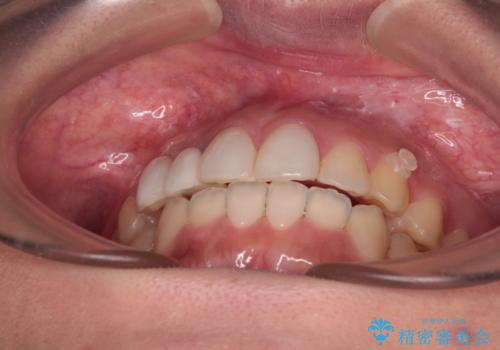

前歯のデコボコが気になる インビザラインによる矯正治療

- 上下前歯のデコボコを気にして来院された患者様です。

インビザラインによる上下歯列の拡大と、IPR(歯と歯の間を削る)にるスペースの獲得により、前歯のデコボコを改善することとしました。